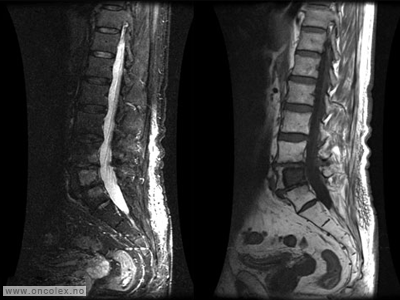

Bildeeksempler på benmargskreft